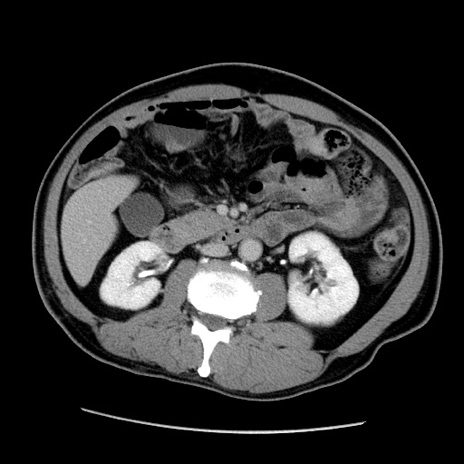

症例22(横断像)

【症例】50歳代男性

【主訴】腹痛

【現病歴】AVMからの被殻出血のため回復期リハ病棟入院中。 本日午後3時頃急に下腹部痛が出現した。

【既往歴】AVM、被殻出血、虫垂炎、高血圧

【身体所見】意識晴明、左半身不全麻痺、会話の理解は良好、36.5°C、腹部:膨隆、全体に板状硬、下腹部正中に圧痛点あり、反跳痛-、筋性防御不明、右下腹部にope scar

【データ】WBC 9400、CRP 0.06